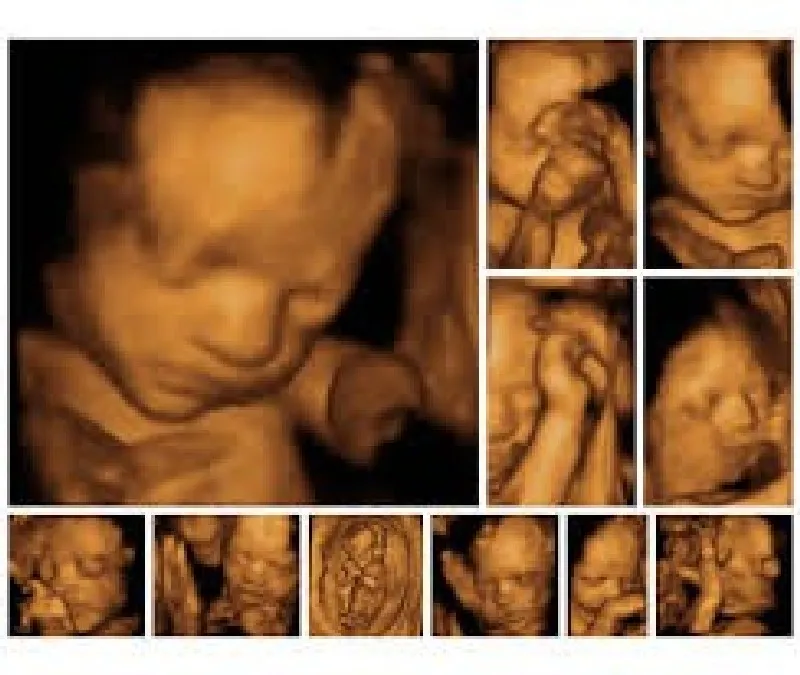

Com a possibilidade de ser alugada com uma empresa de outsourcing de impressão de alta confiabilidade, a impressora de ultrassom proporciona que as imagens deste exame, formadas por meio das ondas sonoras emitidas e captadas durante o processo, sejam impressas em alta qualidade no papel fotográfico, eliminando a necessidade de impressão em filme dry. O processo realizado com a impressora de ultrassom é veloz e permite que o profissional de medicina altere as imagens do exame antes da impressão, melhorando elementos como cor e contraste. Todos estes fatores contribuem para um diagnóstico mais rápido e preciso, o que beneficia o paciente e otimiza o tratamento.